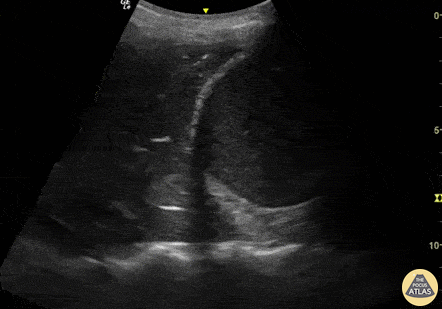

Pulmonary - PLAPS pneumonia

This is a lung ultrasound image in PLAPS view in which we appreciate a consolidation pattern including dynamic air bronchograms as well as a small pleural effusion. The PLAPS view with these findings is a highly sensitivity and specificity for the diagnosis of pneumonia. Renato Tambelli, Emergency Physician Hospital das Clínicas de Marília @R_Tambelli